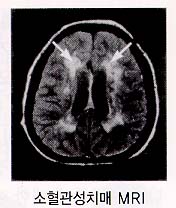

2. Ç÷°ü¼ºÄ¡¸Å Ç÷°ü¼º Ä¡¸Å¶õ ³úÇ÷°üÁúȯ¿¡ ÀÇÇÑ ³ú¼Õ»óÀÌ ´©ÀûµÇ¾î ³ªÅ¸³ª´Â Ä¡¸Å¸¦ ¸»ÇÕ´Ï´Ù. À§ÇèÀÎÀڷδ °íÇ÷¾Ð, ´ç´¢º´, °íÁöÇ÷Áõ, ½ÉÀ庴, Èí¿¬, ºñ¸¸À» °¡Áø »ç¶÷¿¡°Ô¼ ¸¹ÀÌ ³ªÅ¸³³´Ï´Ù. ±× Áß¿¡¼µµ °íÇ÷¾ÐÀÌ °¡Àå ¹«¼¿î À§Çè¿ä¼ÒÀÔ´Ï´Ù.

Á¤»óÀûÀÎ Ç÷°üº®Àº ¸»¶û¸»¶ûÇϰí Åõ¸íÇѵ¥ °íÇ÷¾ÐÀÌ ¿À·¡ Áö¼ÓµÇ¸é Ç÷°üº®ÀÇ ±ÙÀ°ÃþÀÌ µÎ²¨¿öÁý´Ï´Ù. ÀÌ·¯ÇÑ ±ÙÀ°ÃþÀº Ç÷°ü ¾ÈÂÊÀ¸·Î ¹ß´ÞÇÏ°Ô µÇ±â ¶§¹®¿¡ °á±¹Ç÷°üÀÌ Á¼¾ÆÁö°Ô µË´Ï´Ù. Å« Ç÷°üÀÌ ¸·È÷°Å³ª ÅÍÁö¸é ¹Ý½ÅºÒ¼ö, ¾ð¾îÀå¾Ö µî ±Ý¹æ ´«¿¡ º¸ÀÌ´Â Àå¾Ö°¡ ³ªÅ¸³ª°í, ÀÌ·± ³ú°æ»öÀÌ ¹Ýº¹µÉ °æ¿ì ´Ù¹ß¼º ³ú°æ»ö¼º Ä¡¸Å°¡ ¹ß»ýÇÏ°Ô µË´Ï´Ù. ÀÌ¿¡ ¹ÝÇØ ÀÛÀº Ç÷°üÀÌ ¼Õ»óµÇ¸é ±× ¼Õ»óµÇ´Â ³ú¼¼Æ÷ÀÇ ¾çÀÌ ¸Å¿ì ¼Ò·®À̱⠶§¹®ÀÌ ´«¿¡ ¶çÁö ¾Ê°Ô µÇ°í ÀÌ·± º¯È°¡ ´©ÀûµÇ¾î °á±¹ ¼ÒÇ÷°ü¼º Ä¡¸Å¿¡ À̸£°Ô µË´Ï´Ù.

°Ë»ç¿¡´Â Ç÷¾×°Ë»ç, ´¢°Ë»ç, ÈäºÎ¹æ»ç¼±°Ë»ç, ½ÉÀüµµ ³úÆÄ°Ë»ç ¹× ÀÚ±â°ø¸í°Ë»ç(MRI) µîÀÌ ÀÖ½À´Ï´Ù. Ä¡¸Å Áõ»óÀÌ ÀÖÀ¸¸é¼ ½Å°æÇÐÀû °Ë»ç»ó ÀÌ»ó¼Ò°ßÀÌ ÀÖ°í ³ú ÃÔ¿µ»ó ±× ÀÌ»ó¼Ò°ßÀ» µÞ¹ÞħÇÒ ¼ö ÀÖ´Â ¼Ò°ßÀÌ º¸À̸é È®ÁøÇÒ ¼ö ÀÖ½À´Ï´Ù.

»ó±â ¿°ÅÇÑ Ç÷°ü¼º Ä¡¸ÅÀÇ À§Çè¿ä¼Ò, ƯÈ÷ °íÇ÷¾Ð ȯÀÚ¿¡¼ ½Å°æÇÐÀû ÀÌ»ó¼Ò°ßÀÌ ÀÖ°í ±â¾ïÀå¾Ö µî »ç°í·ÂÀÇ ÀúÇϰ¡ ÀÇ½ÉµÉ ¶§´Â ÀÏ´Ü Ç÷°ü¼º Ä¡¸ÅÀÇ °¡´É¼ºÀ» »ý°¢Çϰí Ä¡¸Å Àü¹®º´¿øÀ» ¹æ¹®Çϰųª ³ú ÀÚ±â°ø¸í¿µ»óÃÔ¿µÀ» ½Ç½ÃÇÏ¿©¾ß ÇÕ´Ï´Ù.